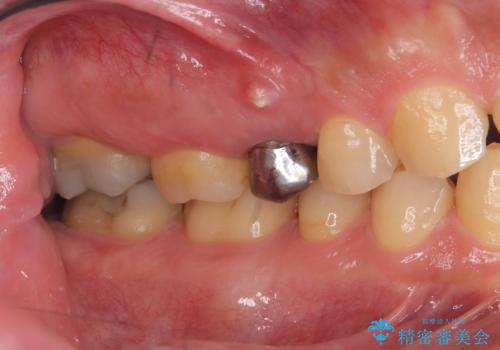

- 「歯茎にニキビみたいのが出来て歯が揺れている」を主訴に来院された患者様です。

右上5番が根尖性歯周炎と歯周病が同時に併発しており、骨が大きく溶け、歯の動揺も著しかったため保存困難と判断をし抜歯してインプラントで治療を行いました。

インプラントはインプラント周囲炎になりにくいスクリュータイプを使用しています。

従来のインプラント治療では、オペを二回に分けることが主流でしたが今は1回のオペで治療を終える事が出来るようになりました。

インプラントと骨が強度にくっつくように骨密度を上げながらドリリングを行っているのと、患者様の骨の状態に合わせてインプラントの形態を選ぶことで可能となっています。